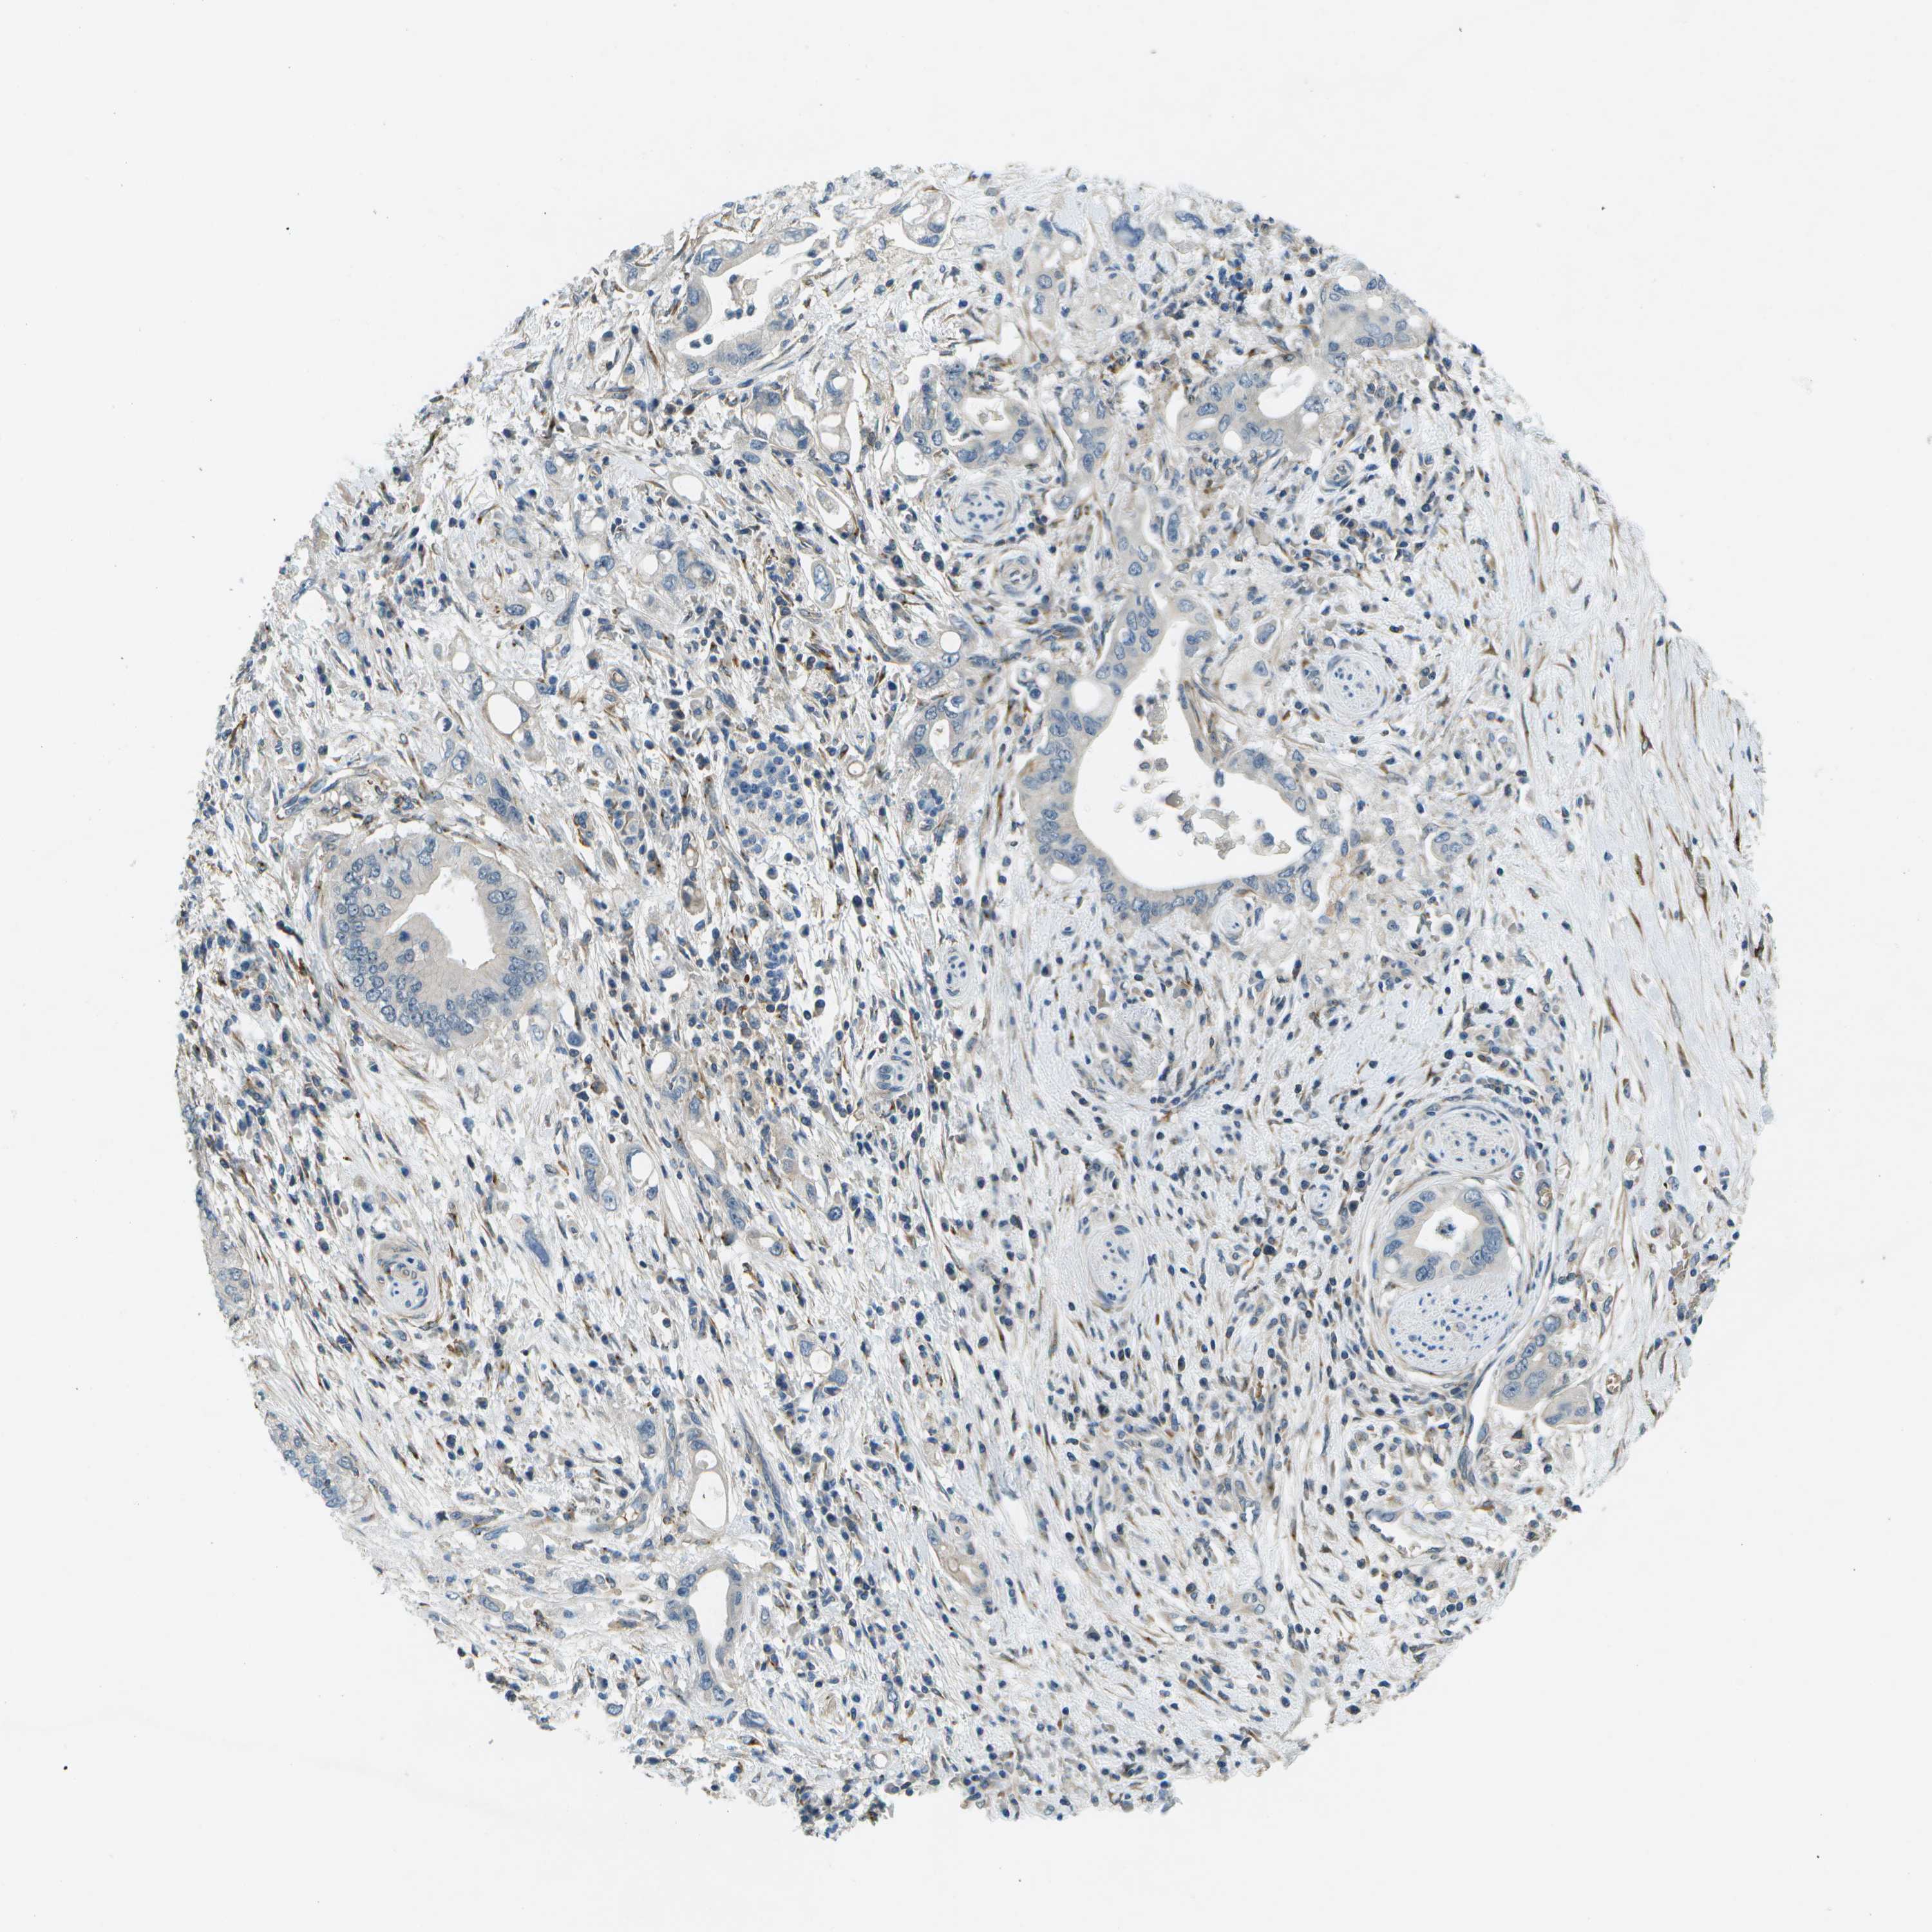

PANCREATIC CANCER - Protein expressioni

A mouse-over function shows sample information and annotation data. Click on an image to view it in a full screen mode. Samples can be filtered based on level of antibody staining by selecting one or several of the following categories: high, medium, low and not detected. The assay and annotation is described here.

Note that samples used for immunohistochemistry by the Human Protein Atlas do not correspond to samples in the TCGA dataset.

Antibody stainingi

Antibody staining in the annotated cell types in the current human tissue is reported as not detected, low, medium, or high, based on conventional immunohistochemistry profiling in selected tissues. This score is based on the combination of the staining intensity and fraction of stained cells.

Each image is clickable and will lead to virtual microscopy that enables deeper exploration of all samples and also displays staining intensity scores, fraction scores and subcellular localization as well as patient and tissue information for each sample.

Antibody HPA016865

Antibody HPA024801

Adenocarcinoma, NOS